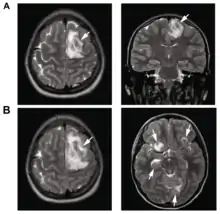

.png.webp)

B: T1-weighted MRI showing expansion of the brain lesions 4 days later

| T2-weighted MRI showing a necrotic brain absess as a result of GAE caused by an infection of Acanthamoeba, genotype T18 | |